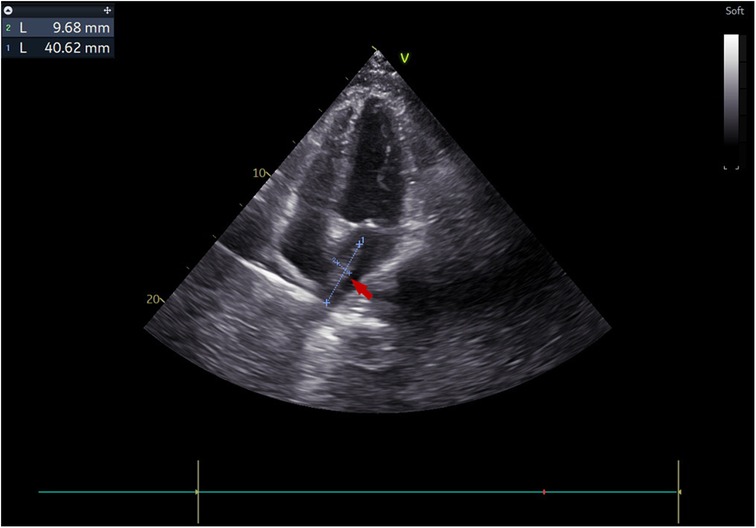

Figure 2

Transthoracic echocardiography visualized a 4 × 1 cm pedunculated vegetation (arrow) in the left atrium in the apical four-chamber view.

The treatment timeline for this patient is shown in (Figure 1). A 38-year-old male with a history of autoimmune lymphoproliferative syndrome (ALPS) and secondary hemophagocytic lymphohistiocytosis (HLH) underwent allo-HSCT on January 12, 2025. Post-HSCT course in the protective isolation unit was uneventful. Following isolation unit discharge on February 10, he developed persistent fever. Plasma metagenomic next-generation sequencing (mNGS) detected V. volvacea DNA (15 copies/μl). Oral voriconazole was initiated on the same day for suspected fungemia. On March 1, his fever escalated to 39°C. Repeat mNGS testing reveals a marked increase in fungal load (1,137 copies/μl). He was then diagnosed with IFIs and treated with intravenous amphotericin B and voriconazole starting March 3. Fever control was achieved in 2 days. On March 11, the peripheral blood fungal load reduced to 2 copies/μl. On March 15, the patient experienced a new-onset mid and lower back pain. A contrast-enhanced CT was performed to revel multiple emboli in the right parietal lobe of the brain and both kidneys. Transthoracic echocardiography (TTE) demonstrated a 4 × 1 cm left atrial vegetation arising from the right inferior pulmonary vein (RIPV) (Figure 2).